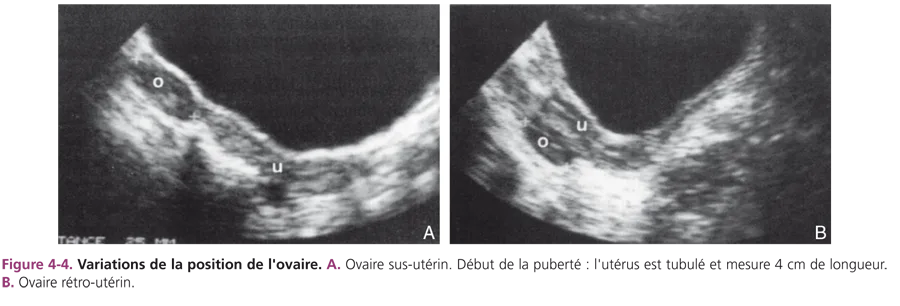

Les critères du développement ovarien tenant compte de la taille et de l’échostructure de l’ovaire sont plus difficiles à définir. Rappelons la difficulté à visualiser l’ovaire, souvent haut situé dans le pelvis, nécessitant une bonne réplétion vésicale. Si l’utérus est latérodévié, l’ovaire du même côté est difficilement perçu. Il peut être en position sus- ou rétroutérine (fig. 4-4). À la période néonatale, la taille de l’ovaire est fonction du développement folliculaire lié à la stimulation hormonale gonadotrope maternelle. Plusieurs follicules (taille supérieure à 5 mm) sont visibles, hypo- ou anéchogènes (fig. 4-5). Comme pour l’utérus, cet aspect est transitoire. Les kystes folliculaires (diamètre supérieur à 20 mm) sont fréquents pendant la grossesse et à la période néonatale.

Fig 4-4